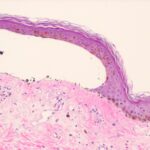

In epidermal EB, which includes EB simplex, EB offeet and hands of Weber and Cockayne , and EB herpetiform is (Dowling-Meara) , the primary separation in experimentally induced blisters always occurs within the basal cell layer. Spontaneously arising blisters may be found subepidermally as the result of complete disintegration of the basal cell layer; in bullae of more than 1 day’s duration, the cleavage may be found intraepidermally or subcorneally as a result of epidermal regeneration . In sections stained with the PAS technique, the PAS-positive basement membrane zone is located on the dermal side of the blister . |

In junctional EB, the trauma of having a specimen taken for biopsy generally is sufficient to induce separation. This separation is located between the epidermis and the dermis, with |

the PAS-positive basement membrane zone usually remaining with the dermis . In some cases of EB letalis, autopsy has revealed extensive subepithelial separation also in the gastrointestinal, respiratory, and urinary tracts . There are no morphologic or enzymatic abnormalities to distinguish the atrophic benign form of junctional EB from EB letalis . |

In EB dystrophica-dominant and EB dystrophica-recessive, light microscopy shows dermal-epidermal separation. A PAS stain is of little help in ascertaining the exact level of cleavage because the PAS-positive basement membrane zone often appears hazy . If recognizable, it is seen in contact with the detached epidermis or appears split. In EB dystrophica-dominant, scarring is mild. However, in generalized EB dystrophica-recessive, extensive erosions may occur, resulting in ulcerations and severe scarring. Severe oral involvement can lead to esophageal stenoses (181). In especially severe cases, death may occur. The ulcers and scars of the skin, mouth, and esophagus may give rise to squamous cell carcinomas, which tend to metastasize . |